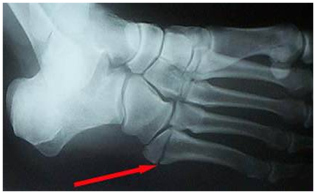

F) FRACTURES DE L’AVANT PIED

Fractures de la base de M5

Si peu déplacée, traitement orthopédique possible

Si déplacée, traitement chirurgical car risque de pseudarthrose